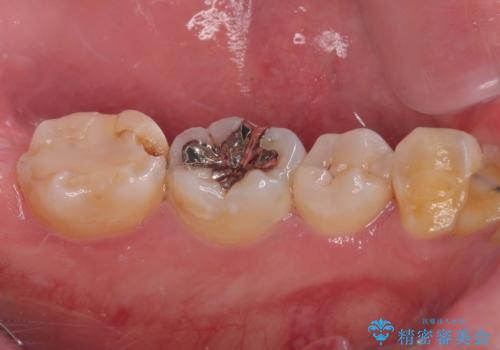

- 詰め物が欠けて虫歯になっていることを気にして来院された患者様です。以前に保険のプラスチックの治療を行われていた状況でした。

歯と歯が接しているところの虫歯のため、セラミックの詰め物(セラミックインレー)での治療を進めていくことにしました。

歯と歯の間の虫歯の治療について

歯と歯の間の虫歯をコンポジットレジンや保険のメタルインレーで治すと段差ができたりして清掃性が悪くなるので、セラミックインレー修復やゴールドインレー修復などの適合の良い詰め物で治療することをオススメします。